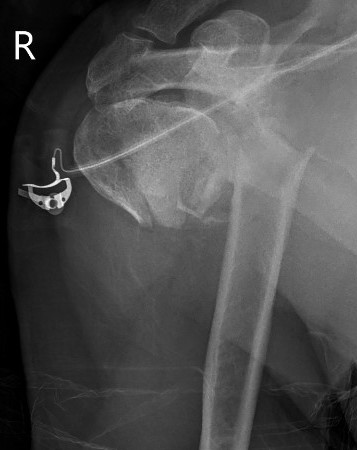

Prosthesis

Remove and size anatomical neck

- identify diameter and thickness

- ream humerus and trial stem

Humeral height

- trial with arm hanging to replicate weight

- will usually need to leave stem proud from fracture

- should be able to anatomically restore tuberosities

- cement stem with retroversion of 30o

Repair tuberosities to the humeral stem